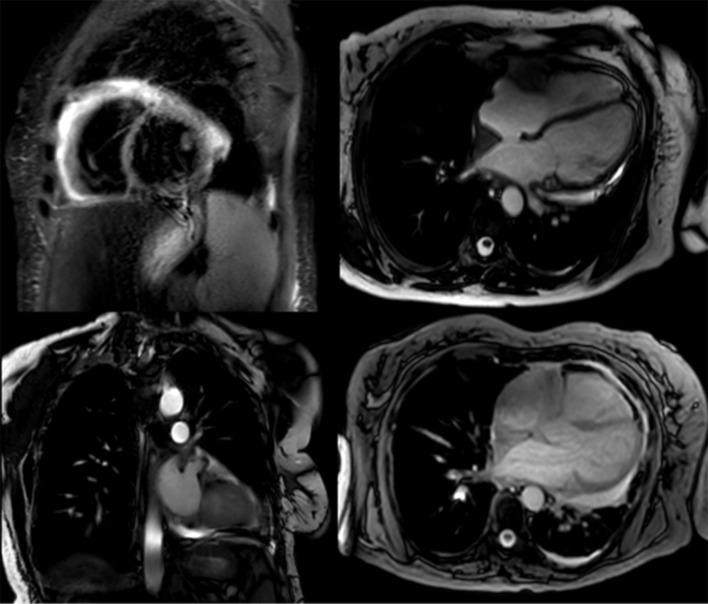

Erdheim-Chester disease (ECD) is a rare non-Langerhans cell histiocytosis characterized by systemic xanthogranulomatous infiltration. We described the case of a female adult presenting with pericardial effusion. Pericardial infiltration is the most frequent cardiac manifestation of ECD and is the one discussed in this article. We found that the majority of patients with pericardial infiltration needed a cardiovascular procedure.

Erdheim-Chester病(ECD)是一种罕见的非朗格汉斯细胞组织细胞增多症,其特征为全身性黄色瘤样肉芽肿浸润。我们描述了一例出现心包积液的成年女性病例。心包浸润是ECD最常见的心脏表现,也是本文所讨论的内容。我们发现,大多数有心包浸润的患者需要进行心血管手术。